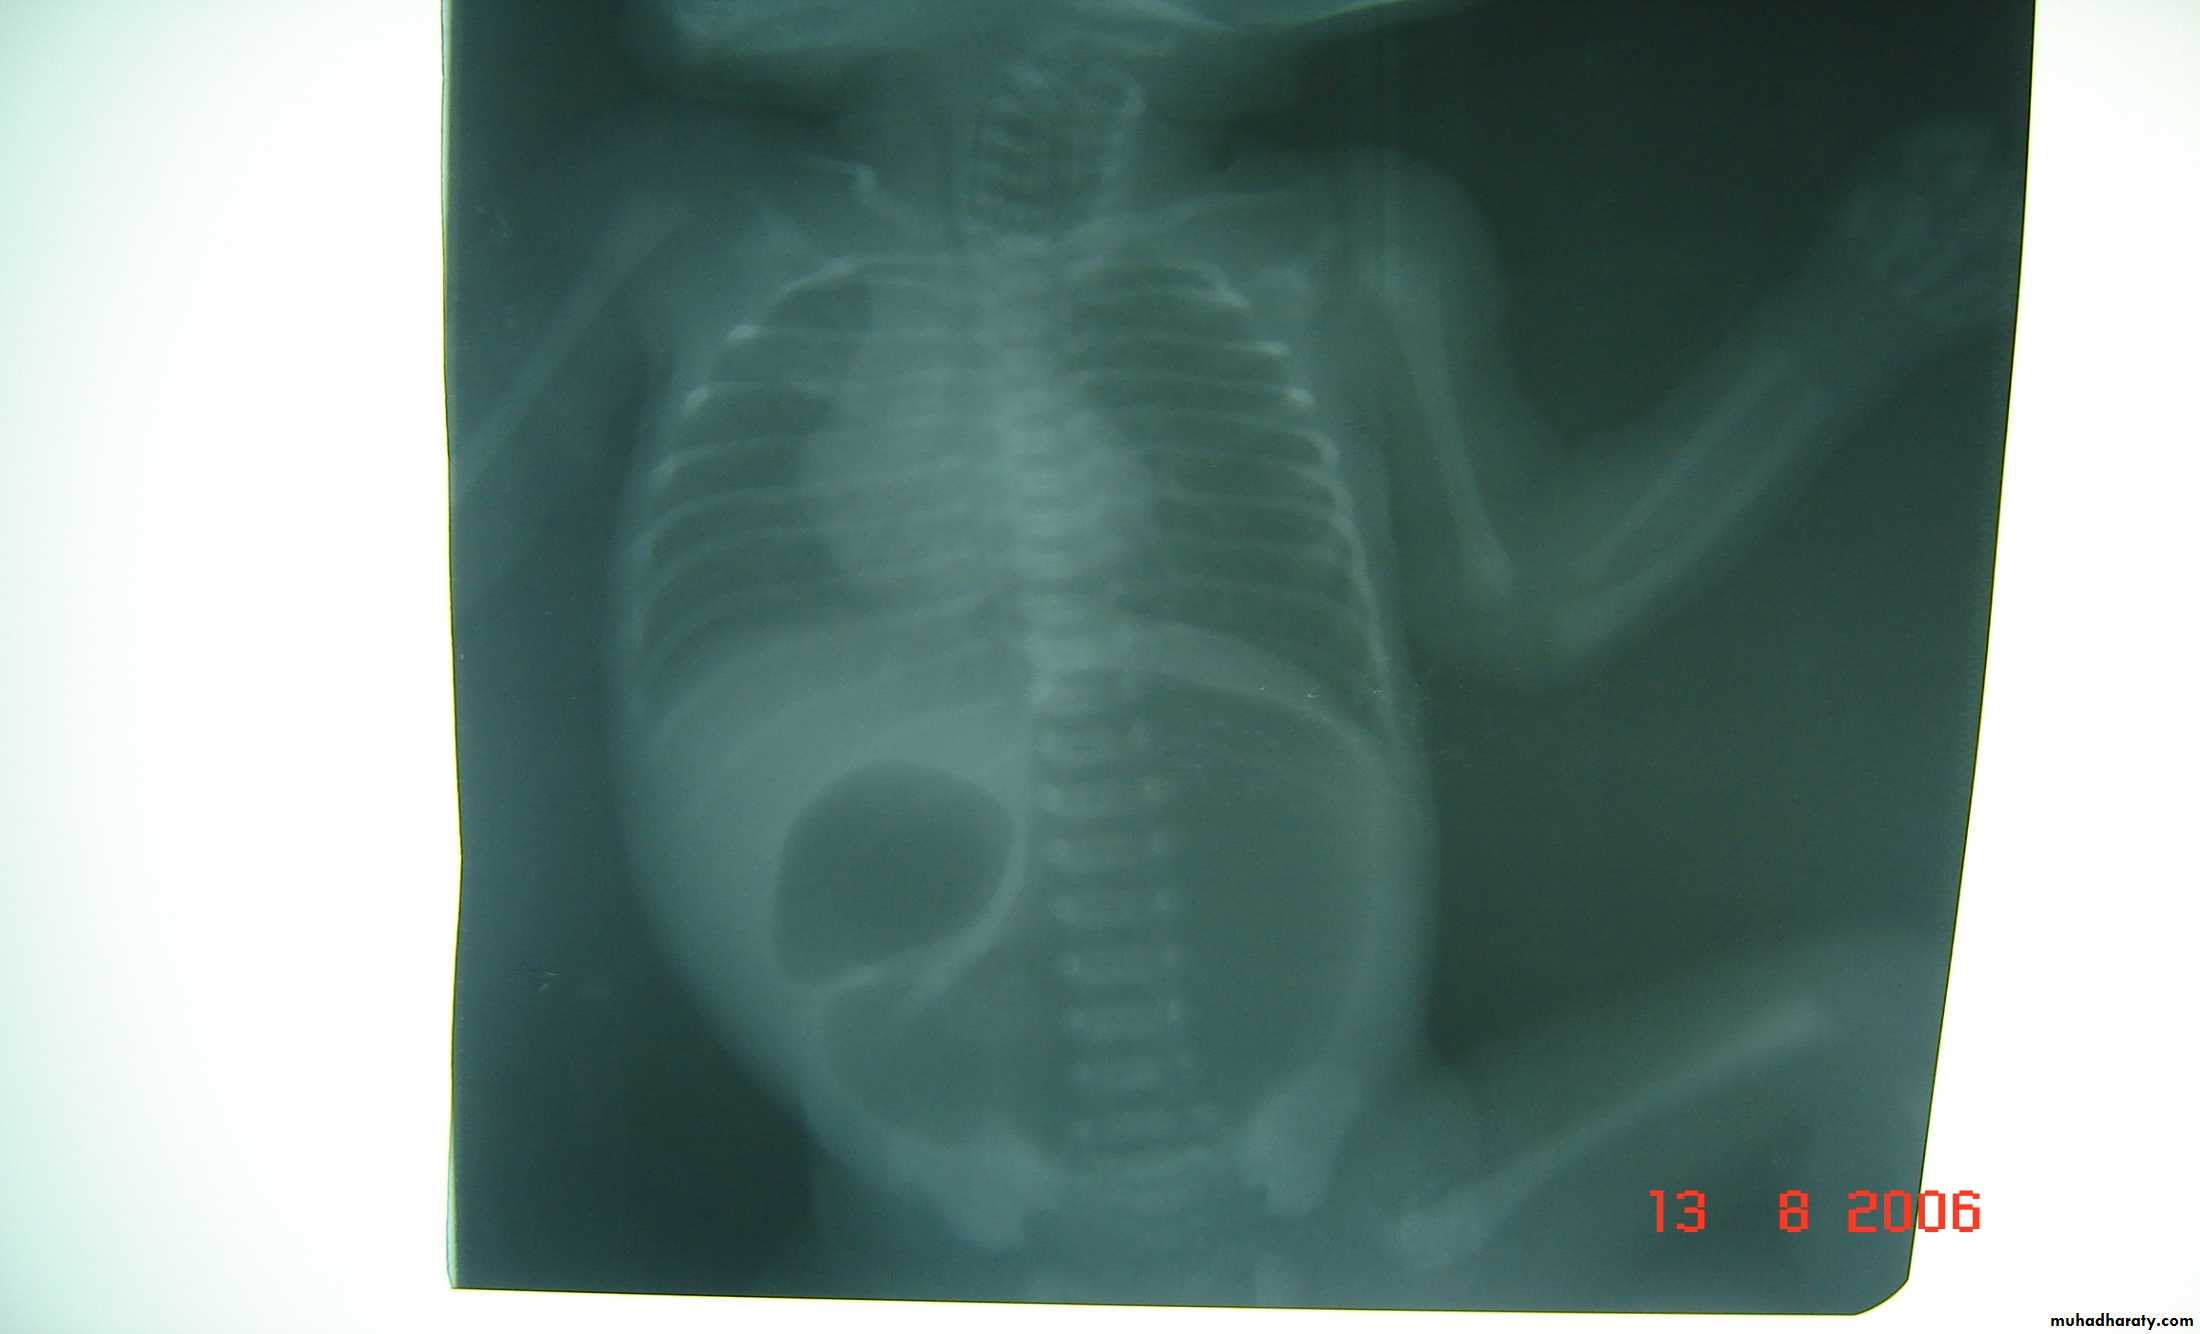

Bowel Obstruction

Meconium ileus